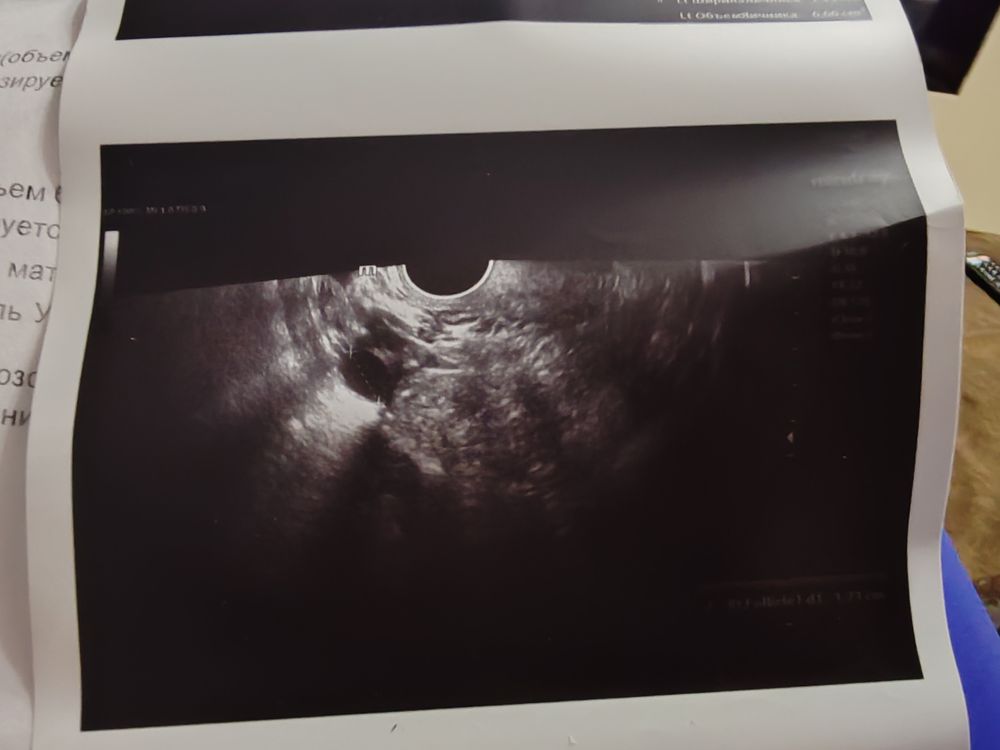

Результаты УЗИБыла стимуляция летрозолом. УЗИ контроль и в чт намеряла узистка дф 17 мм, в субботу укололи овитрель, т.е вчера.

И сегодня шок. Была на УЗИ в правом пя Два дф 16 мм, один с яйценосным бугорком. Неужели они теперь не лопнут? Неужели сдуются из-за ошибки узистка.

Ольга, могу даже фото скинуть где чётко 2 фолликула, и на одном яйценосный бугорок. Второй бы так быстро не вырос

Наталья, посмотрела. Если честно разницы особой между первым и вторым фото не увидела. Разница в 1-2 мм это норма. Даже в один день могут так измерить. Тут вопрос в другом , почему фолликул с чт до вскр не вырос совсем. И по фото к сожалению не очень понятно на счет второго доминантного фолликула. На первом фото четко видно один. На фото с вскр я если честно тоже вижу только один фолликул. Что под ним внизу по фото не понятно. Надо смотреть в живую. Раз есть бугорок по идее должен лопнуть. Вопрос только будет ли он достаточно созревшим( И увидела что эндометрий маловат. Принимаете что то из эстрогенов для эндометрия ?